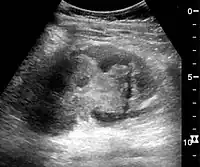

In medical imaging, the acute changes in the kidney are often examined with renal ultrasonography as the first-line modality, where CT scan and magnetic resonance imaging (MRI) are used for the follow-up examinations and when US fails to demonstrate abnormalities. In evaluation of the acute changes in the kidney, the echogenicity of the renal structures, the delineation of the kidney, the renal vascularity, kidney size and focal abnormalities are observed.[16] CT is preferred in renal traumas, but US is used for follow-up, especially in the patients suspected for the formation of urinomas. A CT scan of the abdomen will also demonstrate bladder distension or hydronephrosis.

- Renal ultrasonograph in renal failure after surgery with increased cortical echogenicity and kidney size. Biopsy showed acute tubular necrosis.[16]